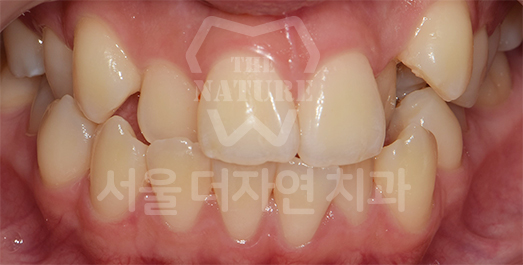

Impacted Tooth Solution

An impacted tooth remaining within the alveolar bone can cause damage to adjacent teeth.

Orthodontic traction is used to guide the impacted tooth into its correct position,

allowing it to erupt and seat normally within the dental arch.

BEFORE: 2011.08.12

-